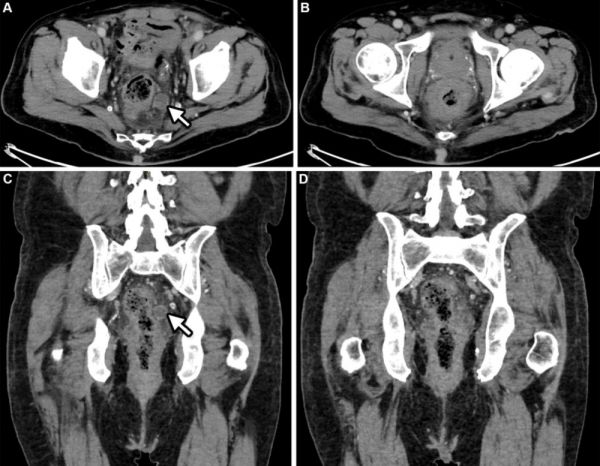

大多数猴痘患者的病变位于肛门生殖器区域,超过一半的患者病变位于躯干或四肢,但病变也可能集中在手掌、足底和面部。其他症状包括发烧、淋巴结肿大、咽炎、头痛、嗜睡、肌痛、直肠炎或肛门直肠疼痛。皮疹或病变持续2~3周,开始为斑疹,发展为丘疹、水疱,然后形成脓疱,结痂、脱落,并可能留下疤痕。

一名男性猴痘患者直肠炎的影像。